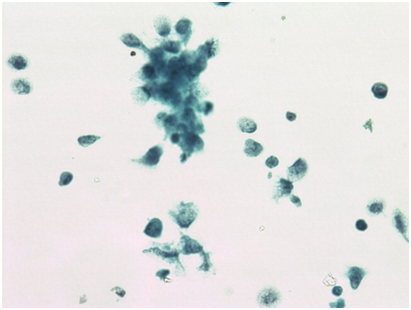

We report a case of 62 years female menopausal for 17 years operated for endometrial adenocarcinoma grade II (moderately differentiated). She underwent total abdominal hysterectomy & bilateral salpingoopherectomy. Then she received 35 cycles of brachytherapy. One year later she consulted for a cutaneous mass measuring 4x4cm, firm too hard, fixed at anterior left shoulder. FNAC was performed along with Liquid based cytology. Smears examined were cellular comprising neoplastic cells arranged in groups, sheets, acinar structures and dispersed singly having round to oval, moderately pleomorphic nuclei coarse nuclear chromatin, prominent nucleoli and moderately abundant cytoplasm which is vacuolated at places. Keeping in view previous histopathological diagnosis of endometrioid adenocarcinoma diagnosis of metastasis possibly from endometrial adenocarcinoma was made. Liquid based cytology also reveals groups, clusters & acini of these neoplastic cells in a relatively clean background. Immunocytochemistry (ICC) for Progesterone Receptor (PR) was negative on LBC smears suggesting poor prognosis. Then patient was further investigated and Ultrasonography (USG) abdomen, Contrast enhanced chest tomography (CECT) chest, abdomen & pelvis & haematological tests were performed. USG show hypoechoiclesion with areas of cavitation right lobe revealing metastasis. CECT show multiple heterogeneously enhancing hypodense lesion in right lobe of liver (metastasis), mediastinal & retroperitoneal lymphadenopathy, metastasis right lobe of lung & enhancing mass pre & paraaortic region. Based on FNAC report and clinical investigatory correlation patient was started with chemotherapy & radiotherapy (Figures 1-5).

Figure 3 Malignant cells with moderate to marked cytoplasm with mitotic figure (400X).

Figure 4 LBC showing gland formation (200X).